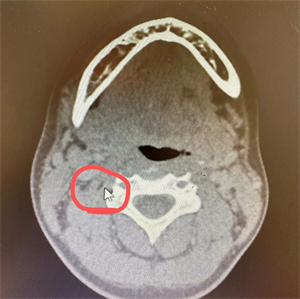

小李同学(化名),13岁在放学途中不慎摔倒,手中的香肠签子意外自左侧口角插入口腔内,“口腔异物半小时”急诊入住我院口腔科。入院后,经过紧急颌面颈部CT及CTA等一系列检查,发现异物由左侧舌体斜向插入咽部,紧贴颈椎前缘到达右侧颈动脉深面,且异物距离颈动脉仅有3mm,情况十分危急。